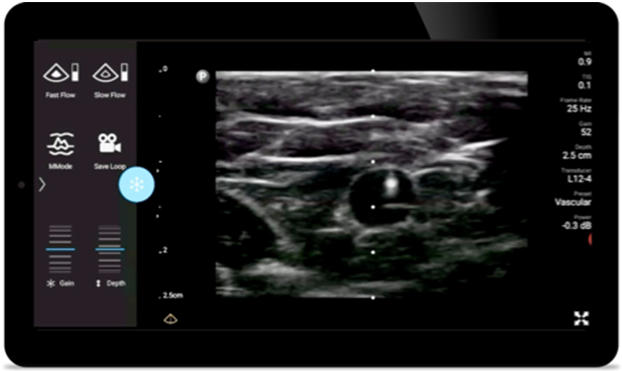

Lumify handheld ultrasound for anesthesiology helps you clearly visualize border definition with your needle placement, surrounding nerves, vessels and fascial planes.

From revealing the subtle details of an image to uncovering enriched tissue definition from multiple angles, Lumify can help you make real-time decisions with more confidence from assessment through recovery.